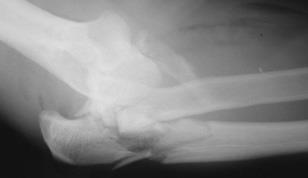

Complex elbow dislocation

A complex dislocation of the elbow. In addition to dislocation, there are multiple fractures of the elbow.

After surgery, the elbow will need to be protected. It may be protected in a splint, or with a hinge on the outside of the arm. These devices protect the elbow from dislocating again.

If blood vessel or nerve injuries are associated with the elbow dislocation, additional surgery may be needed to repair the blood vessels and nerves as well as repair bone and ligament injuries. Physical therapy is often necessary to minimize stiffness. The goal of recovery is to protect the healing elbow while also trying to limit scar tissue and stiffness.  However, some loss of range of motion is to be expected.